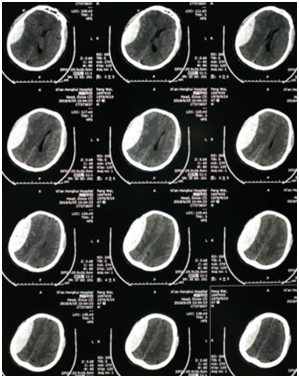

这是一位40岁男性患者,从江苏来到西安打工,在装修时不小心从2米高处坠落,当即昏迷,约10分钟后苏醒,感头晕头痛,一侧眼见淤血青紫肿胀,四肢尚可活动,随后立即送往医院,查头部CT提示颅内硬膜外血肿,量约50ml,因是外地患者,家属不在身边,紧急联系家属以及联系公司老板,在紧张准备过程中,病人病情逐渐加重,意识开始模糊至昏迷,左侧肢体逐渐完全瘫痪,不能活动,立即再次复查头部CT提示颅内出血增加至90ml。随后立即在全麻下进行开颅血肿清除术,仅用1小时余手术顺利结束。术后患者神志清楚,对答切题,约术后4小时候患者左侧肢体可活动,第二天早晨查房,患者左侧肢体已经活动自如,没有遗留任何后遗症。

患者头部CT提示右颞顶硬膜外血肿,量约90ml

患者意识模糊,左侧肢体偏瘫,左眼淤血肿胀